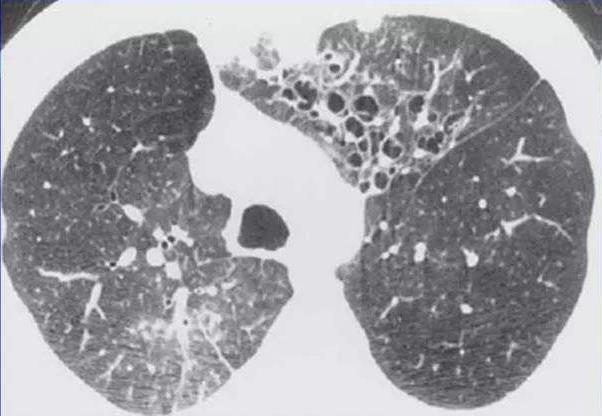

提示肺念珠菌病的影像学征象:结节实变影和(或)大片状实变,少有空洞形成。血行感染或由肺部感染发生播散者,多呈弥漫粟粒状阴影。念珠菌也可引起侵袭性支气管感染,影像学表现同曲霉感染。提示肺孢子菌肺炎的影像学征象:双肺毛玻璃阴影。

(图来源于网络,侵删)